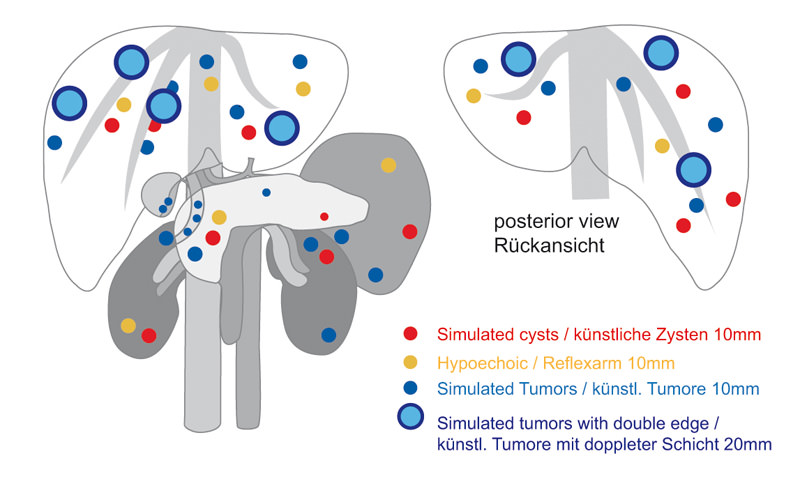

Dieses Übungsmodell der Oberklasse ermöglicht die Übung des Ultraschalls mit den vorhandenen Ultraschallgeräten. Es beinhaltet die Anatomie der Oberbauchorgane sowie viele Pathologien. Das Modell enthält im Einzelnen die Leber (Segmente zu erkennen), Gallengangsystem, Bauchspeicheldrüse, Milz, Nieren und viele vaskuläre Strukturen wie Aorta, Vena Cava, Oberbauchgefäße mit Nebenästen, Portalvene mit Nebenästen, obere Mesenterialgefäße und Nierengefäße. Eine Vielzahl von Zysten und Tumoren im Modell bietet umfassende Übungsmöglichkeiten auch für die fortgeschrittene Diagnostik. Das Phantom kann wie ein menschlicher Körper von allen Seiten geschallt werden.